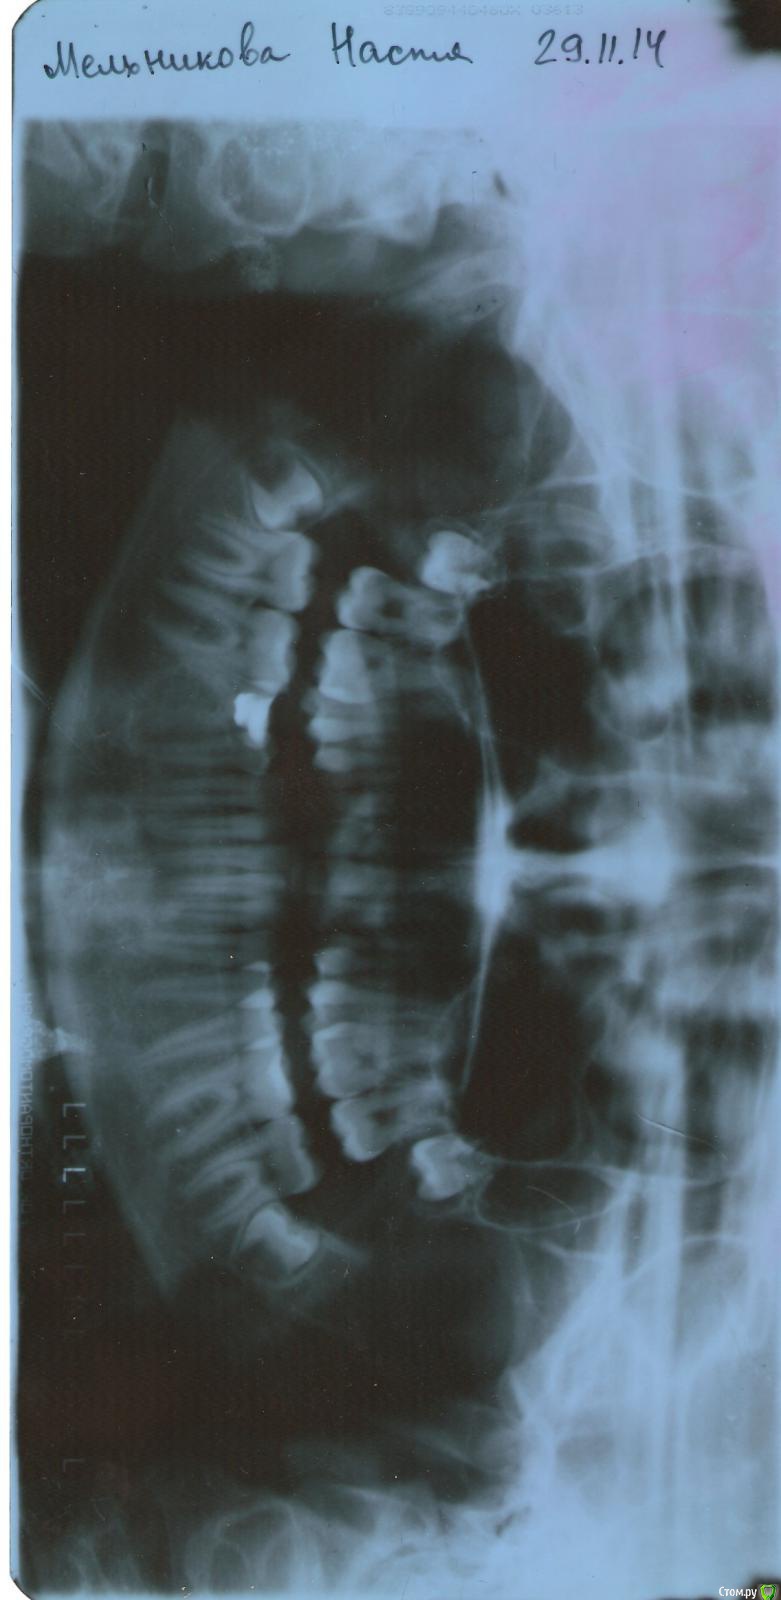

МИрина Опубликовано 25 февраля, 2015 Поделиться Опубликовано 25 февраля, 2015 Добрый день!Моей дочери 16 лет. Перед началом ортодонтического лечения нам назначили удаление нижних восьмерок. Обратились в детскую клинику, где нам составили план лечения. Посмотрев наш снимок, хирург стал настаивать на удалении только с глубокой седацией и только двух зубов сразу ( хотя мы хотим второй удалить позже, через месяц,- нам так наш ортодонт посоветовал). Причем, удаление двух зубов займет по расчетам хирурга 3 часа. Скажите, пожалуйста, действительно ли у нас такой сложный случай, что седация обязательна, неужели действительно по 1,5 часа на зуб? Дочь не боится удалять и наоборот отказывается делать под седацией. Не знаю, как поступить. Возможно, она переоценивает свои возможности, и надо ее уговаривать все-таки на глубокую седацию. Мы собираемся удалять пока один зуб. Прошу Вашего профессионального мнения: сколько по времени(хотя бы приблизительно) занимает удаление одной такой восьмерки? Спасибо. Ссылка на комментарий

МИрина Опубликовано 25 февраля, 2015 Автор Поделиться Опубликовано 25 февраля, 2015 можно и без седацииСпасибо!А по времени сколько в среднем занимает удаление такого зуба у опытного хирурга? Полчаса, час, полтора часа? Если я правильно понимаю - корни еще не сформировались у зуба или я их не вижу в силу некомпетентности? Ссылка на комментарий

AlexanderGudkov Опубликовано 25 февраля, 2015 Поделиться Опубликовано 25 февраля, 2015 Да. Корни не сформировались, удалить такой зуб проще, чем тот, у которого сформировались. Я за местное обезболивание Ссылка на комментарий